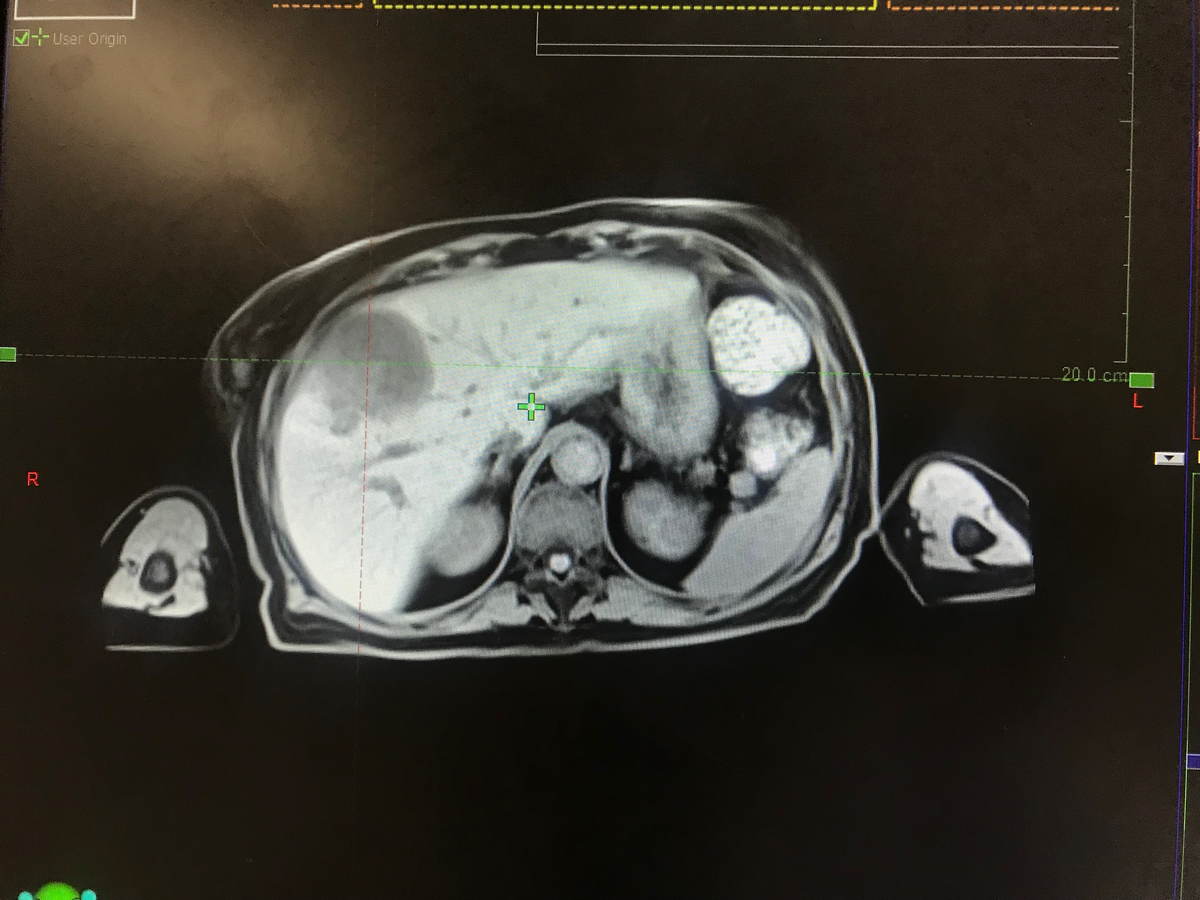

55 years old female, diagnosed of a pancreatic adenocarcinoma in 2017. She underwent a Whipple surgery followed by adjuvant chemoradiation to the tumor bed using a 3 fields 3D-conformal plan.

In 2019, she developed a single liver lesion of 2.5 cm , segment VIII treated with RFA.

3 months after, the lesion progressed in size reaching 7 cm , CA19-9 5000, with no other secondary lesion elsewhere.

Her liver function is maintained, only GGT and ALP are elevated.

Screenshots of her MRI and delineated CT sim are attached below.

GTV acc volume: 291 cc

PTV volume: 436 cc

Liver-GTVacc volume: 1000 cc